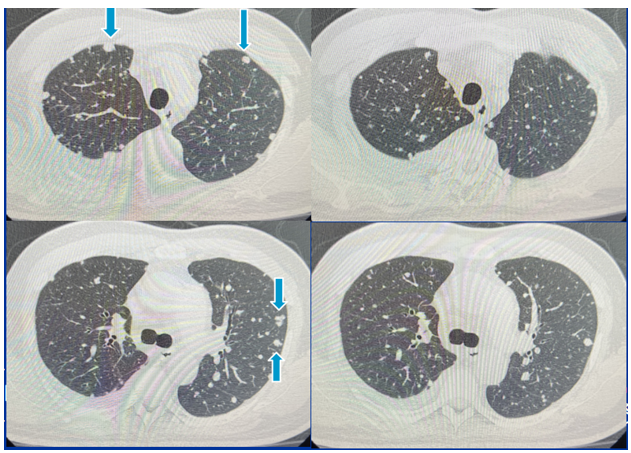

Hình ảnh chụp cắt lớp vi tính ổ bụng sau 3 tháng:

Hình 4: Bên trái: trước điều trị: nốt mờ rải rác 2 bên phổi, kích thước từ 5-10mm. Bên phải: sau điều trị 3 tháng các nốt mờ hai phổi giảm kích thước 3-5mm